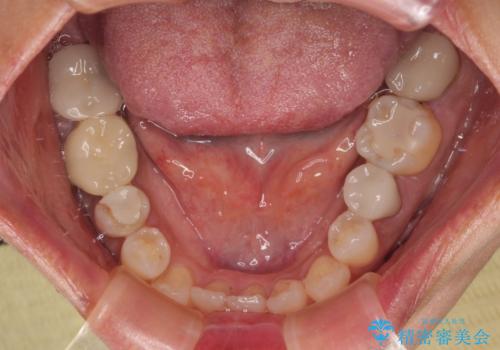

右下のむし歯が歯肉縁下に及んでおり、歯周外科処置(歯冠長延長術)を行った上で、根管治療を行い、状態を整えて補綴治療を行うこととしました。

新幹線で通院をされていたため、極力診療回数を減らして、一度にまとめて多くの処置を行うことで負担を軽減しました。